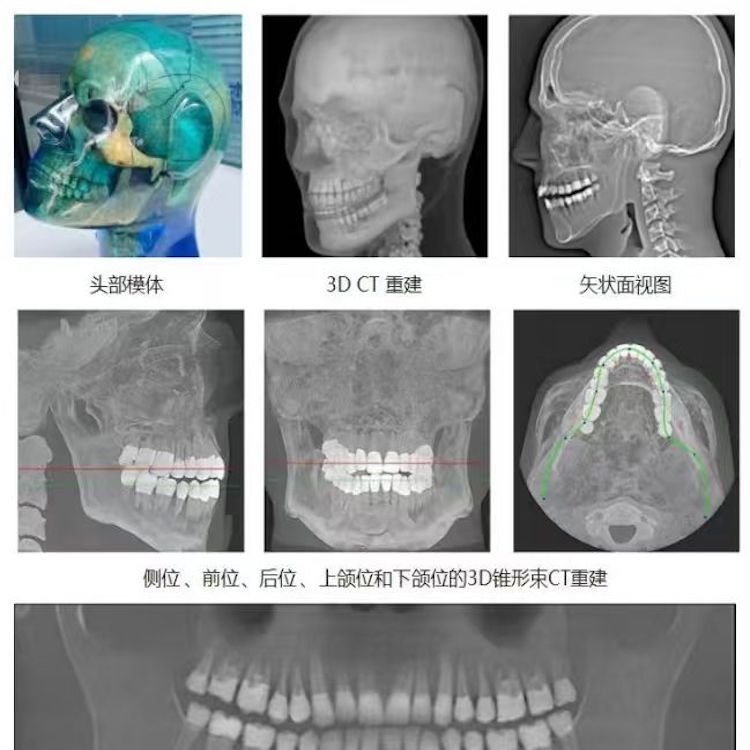

頭部模體是頭部診斷放射學(xué)的參考標(biāo)準(zhǔn),該模體旨在協(xié)助技術(shù)和臨床人員,在大多數(shù)需要精細(xì)解剖細(xì)節(jié)的放射學(xué)程序中選擇、監(jiān)測(cè)、培訓(xùn)和驗(yàn)證掃描參數(shù)。 模體為研究人員、臨床醫(yī)生和技術(shù)人員提供了一致性的工具。它非常適合確定最佳系統(tǒng)設(shè)置、調(diào)試新設(shè)備、監(jiān)測(cè)系統(tǒng)性能和培訓(xùn)牙科X射線、全景X射線、CT和錐束CT程序。 這個(gè)模體包括一個(gè)可調(diào)節(jié)的支架,用于在錐束 CT 或全景X射線系統(tǒng)中定位。模體的下頜略微張開,前牙垂直排列,以復(fù)制正確的咬合引導(dǎo)定位 。 請(qǐng)注意,實(shí)際咬合引導(dǎo)無(wú)法在這個(gè)產(chǎn)品中定位。 頭部模體是由專有組織等效材料制成的。由組織模擬樹脂制成,這些樹脂模擬X射線對(duì)人體的衰減特性,適用于CT和治療能量范圍(50keV-25MeV)。 模體在大小和結(jié)構(gòu)上都近似于平均男性頭部 。該模體包括詳細(xì)的3D擬人化解剖結(jié)構(gòu), 包括大腦、骨骼、喉、氣管、鼻竇、鼻腔和牙齒。骨骼包括皮質(zhì)和骨小梁的分離。牙齒包括明顯的牙本質(zhì)、牙釉質(zhì)和包括神經(jīng)的牙根結(jié)構(gòu)。鼻竇完全張開。

頭部模體特點(diǎn) 1. 詳細(xì)的解剖特征; 2. 確定法蘭克福平面以確保正確對(duì)齊; 3. 50 keV 至 25 Mev 的組織等效值; 4. 具有六個(gè)自由度的定位支架; 5. 包括泡沫內(nèi)襯手提箱; 6. 12個(gè)月保修。

功能和應(yīng)用 1. X射線 ,全景X射線 ,CT和錐束CT系統(tǒng); 2. 學(xué)習(xí)如何正確定位頭部以獲得最佳圖像; 3. 測(cè)試重建技術(shù)和算法 ,用于植入物規(guī)劃和頜面部重建; 4. 在實(shí)施新設(shè)備和新技術(shù)期間培訓(xùn)并評(píng)估人員; 5. 驗(yàn)證圖像質(zhì)量的一致性。